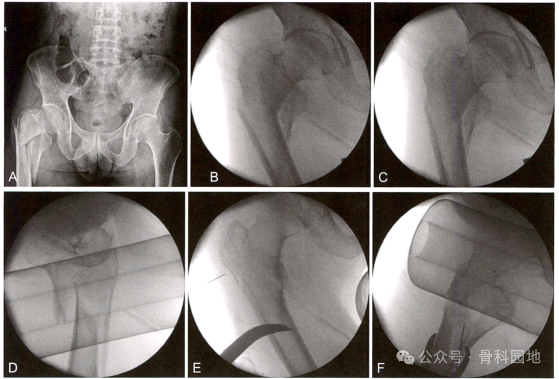

股骨转子下骨折近端常见的畸形是外展、屈曲和外旋。然而,粉碎性骨折可以改变作用于主要股骨近端的力。比如大转子和/或小转子的移位骨折可以减轻这些变形力。如下图:

与大多数骨折一样,了解骨折类型很重要,重点是识别转子下区域的骨与股骨近端的连续性或整个区域是否粉碎。建议CT扫描进一步描绘骨折类型。

二、复位技术一(参考解放军总医院创伤骨科手术学)

1、外展屈曲移位骨折:

2、近端屈曲畸形的骨折,可以在前方钻入一枚单皮质 Schanz针,连接T形手柄向远端牵拉,下压近端骨块,进行复位;或者在近端骨块外侧和前方经小切口分别置人两枚顶棒,下压并向内顶推复位。

3、近端外展、屈曲的骨折,还可以将髓内钉插人骨折近端,利用髓内钉作为摇杆,控制骨折近端进行复位。但该方法难以控制进针点和进针方向,较少使用。

4、远端向内移位的骨折,可以在远端使用骨钩,同时近端配合顶棒进行复位。